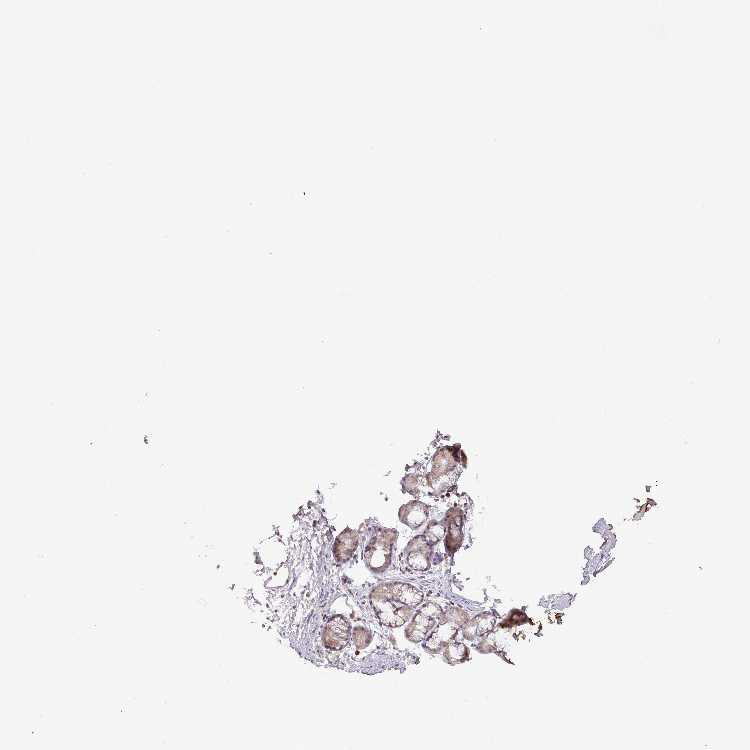

SOFT TISSUE 1 - Antibody stainingi

Antibody staining in the annotated cell types in the current human tissue is reported as not detected, low, medium, or high, based on conventional immunohistochemistry profiling in selected tissues. This score is based on the combination of the staining intensity and fraction of stained cells.

Each image is clickable and will lead to virtual microscopy that enables deeper exploration of all samples and also displays staining intensity scores, fraction scores and subcellular localization as well as patient and tissue information for each sample.

Antibody HPA045007Antibody HPA052115

Chondrocytes MediumMedium

Fibroblasts Not detectedNot detected

Peripheral nerve Not detected-